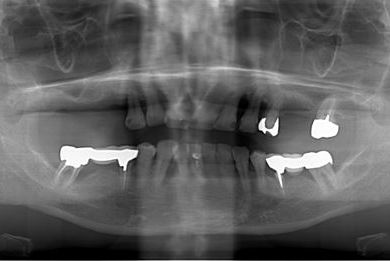

| 性別/年齢 | 女性 / 51歳 | ||||||||||||||||||||||||||||||||

| 主訴 | 他の歯科医院で入れ歯を入れたが、滑舌や味などで不自由を感じている。インプラントは難しいと言われたが、可能かどうかみていただきたい。 | ||||||||||||||||||||||||||||||||

| 治療方針 | サイナスリフトにより上顎洞を拳上し、インプラント治療を可能にする。 | ||||||||||||||||||||||||||||||||

| 治療内容 | インプラント3本(サイナスリフト)、ハイブリッドセラミッククラウン5本 | ||||||||||||||||||||||||||||||||